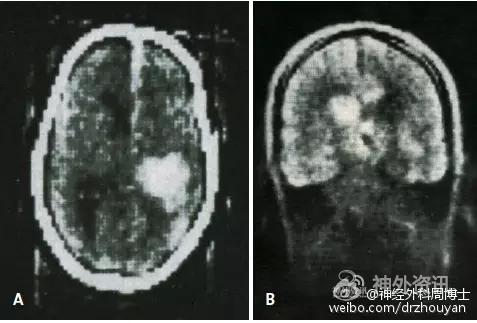

这是一例患有重度脑积水的儿童的脑室造影图像。这张图片发表于1913年Dandy的史无前例的论文中——《脑室内注入空气后的脑室成像技术》。

第一张脑CT片子发表于1973年(A),Hounsfield在他的基础论著《计算机横轴向断层扫描》说明了这项技术。注意观察:左侧基底节区的出血性占位病变使得侧脑室移位。B图为早期的MRI冠状位成像(1980年,诺丁汉)。紧随其后的是核磁共振成像技术,简称MRI。MRI不仅仅能准确的完成诊断,还可以精确的观察不同结构之间的相互解剖关系。